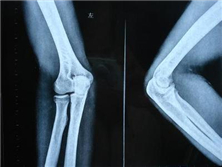

桡骨小头骨折

桡骨小头骨折是一种常见的肘部损伤,占全身骨折0.8#xFF05;,约有l/3患者...